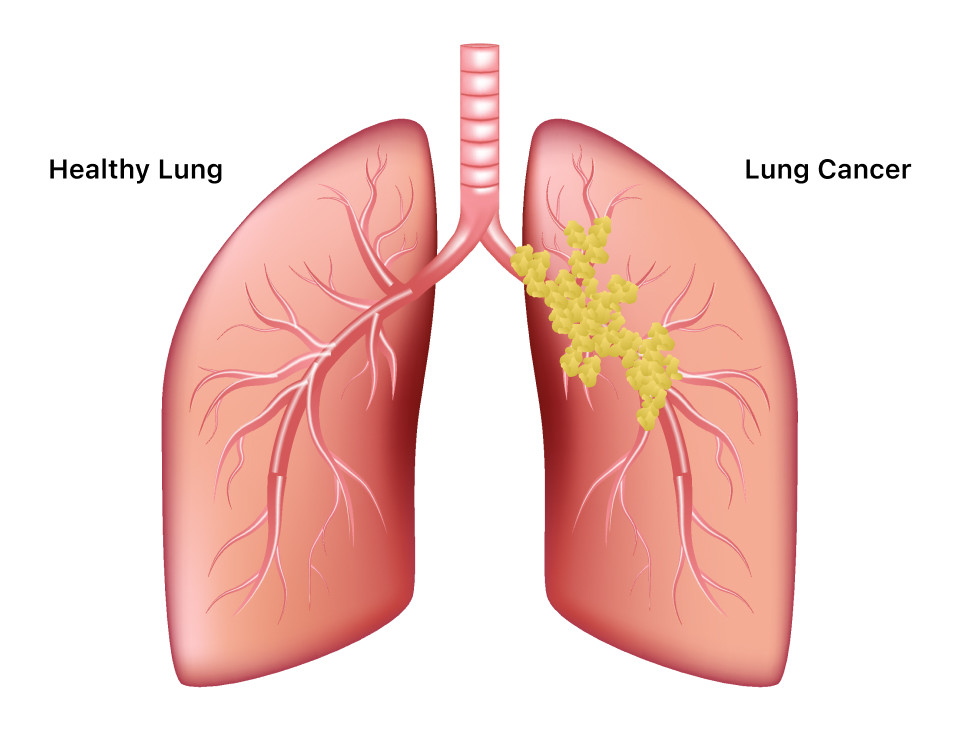

Đặc biệt là bệnh ung thư phổi rất khó phát hiện trong giai đoạn đầu. Ảnh: SCC.